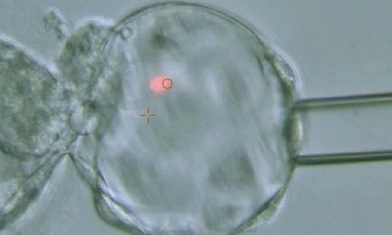

Embryomobile is a totally innovative application from the Marquès Institute. It allows patients to see, via the Internet, the evolution of their embryos in the Embryoscope incubator. They can do this in real time, from the day of In Vitro Fertilization to the day of embryo transfer, five days later

From home or anywhere else, via mobile phone or a device with Internet access, you can observe the same images that embryologists see in the laboratory.

A scientific study by Institut Marquès, presented at several European congresses, has shown that observing embryos in real time through the Embryomobile increases pregnancy rates by up to 11%. Furthermore, analyzing the results, it was found that, as the number of times they observed their embryos increased, the pregnancy rate also increased.